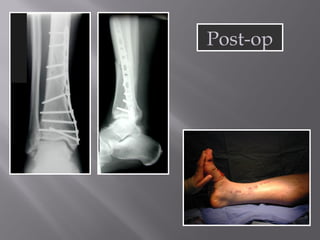

Post-op